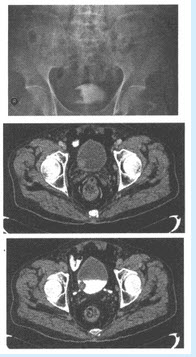

患者,男,65岁,因肉眼血尿2周就诊。无明确原因肉眼全程血尿,无腰痛、下肢水肿,实验室检查:血常规正常,尿常规镜检满视野红细胞,X线平片无异常征象。

第1题,共6个问题

(多选题)根据上述资料,还应该做哪些检查()

A:CT

B:MRI

C:IVP

D:US

E:ECT

F:DSA

第2题,共6个问题

(单选题)患者行IVP及CT检查,图像如下,应考虑患何种疾病()

A:膀胱息肉

B:膀胱癌

C:膀胱横纹肌肉瘤

D:膀胱平滑肌肉瘤

E:膀胱结核

F:膀胱憩室

第3题,共6个问题

(多选题)诊断依据是哪些()

A:IVP右侧膀胱充盈缺损

B:CT膀胱邻近右输尿管息肉样、较宽基底、轮廓不规则肿块

C:右侧输尿管扭曲、扩张

D:临床上全程无痛性血尿

E:老年人

F:盆腔内淋巴结不肿大

第4题,共6个问题

(单选题)诊断该病最敏感、最可靠的是哪些检查()

B:US

C:MRI

D:膀胱镜检加活检

E:IVP

F:KUB

第5题,共6个问题

(多选题)本病应该与哪些疾病鉴别诊断()

A:膀胱结核

B:膀胱息肉

C:输尿管肿瘤

D:子宫肌瘤

E:膀胱转移瘤

F:前列腺增生

第6题,共6个问题

(多选题)膀胱癌从病理上可分为()

A:移行细胞癌

B:鳞状细胞癌

C:腺癌

D:未分化癌

E:原位癌

F:髓样癌